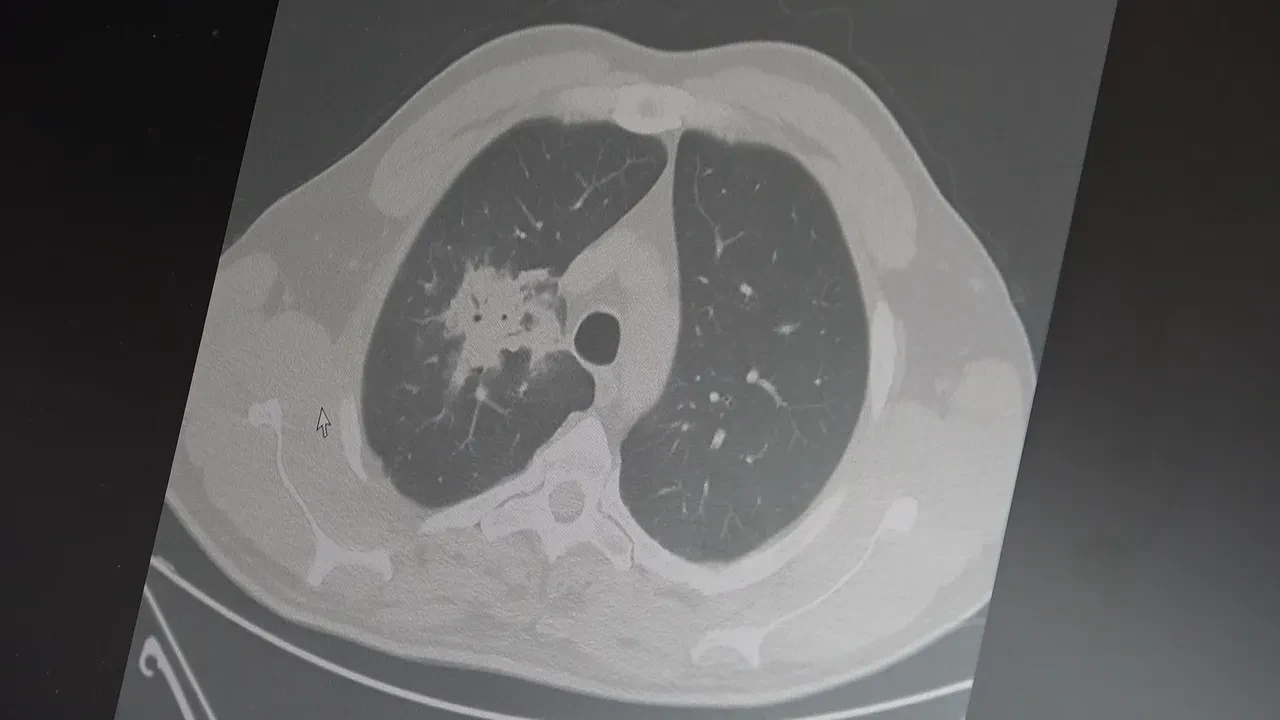

100'den fazla bilimsel çalışmanın incelendiği kapsamlı analizlere dikkat çeken Özkaya, elektronik sigaraların özellikle temas ettiği akciğer ve ağız bölgelerinde kanser riskini artırabileceğine dair güçlü bulgular bulunduğunu belirtti. Uzun vadeli sonuçların henüz tam olarak ortaya çıkmadığını ancak erken uyarı işaretlerinin ciddi olduğunu vurguladı. Araştırmalarda insan, hayvan ve laboratuvar verilerinin birlikte değerlendirildiğini aktaran Özkaya, elektronik sigaraların içerdiği kimyasalların hücre düzeyinde zarara yol açtığının ortaya konulduğunu ifade etti.

2024 yılında yayımlanan bir çalışmaya da değinen Özkaya, hem geleneksel sigara hem de elektronik sigara kullanan bireylerde akciğer kanseri riskinin, sadece sigara içenlere göre dört kat daha fazla olduğunun bildirildiğini kaydetti.